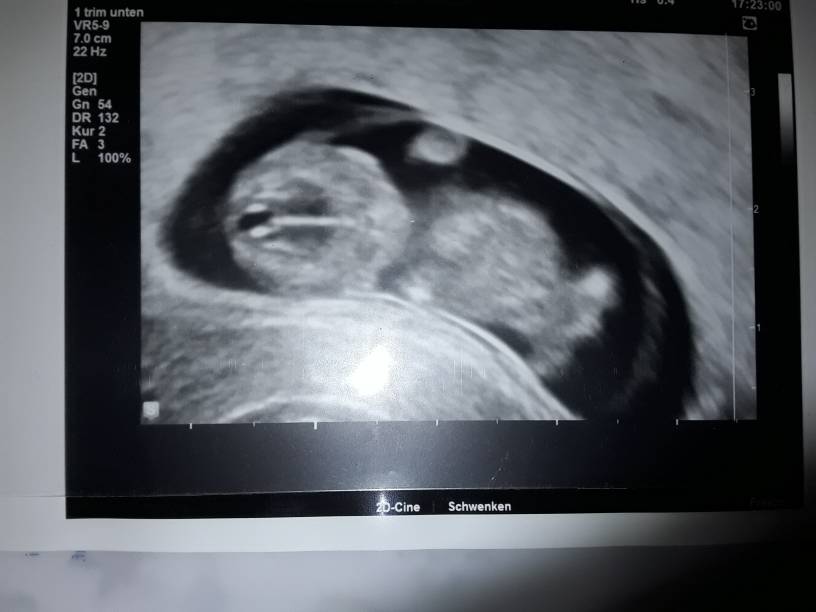

Ja tez jestem po wizycie. Maluszek ma się bardzo dobrze. Machał rączka i nogami. Kręcił się cały czas tak, że ciężko było zrobić zdjęcie gdzie byłby cały widoczny. Na płeć jeszcze za wcześnie, ale to nawet lepiej jak dla mnie. Mówiłam lekarzowi, żeby nie mówił mi za szybko płci. Muszę się przygotować psychicznie.

Termin u nas brany pod uwagę nadal z OM.

20181009_195322.jpg

Roki chyba nie taki duży bo mam tylko 33mm wiesz trochę ponad 3cm jeśli dobrze czytam dane w karcie. Ale lekarz mówił że ponad 3 cm więc chyba dobrze interpretuje. Wg OM 9t6d, a USG 10t5d jeśli dobrze czytałam na monitorze.